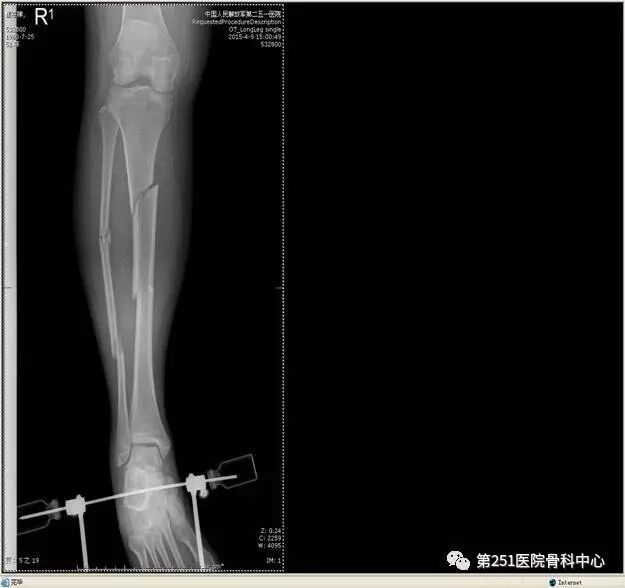

病例1:男性,40岁,车祸伤,胫腓骨多段骨折。

![]()